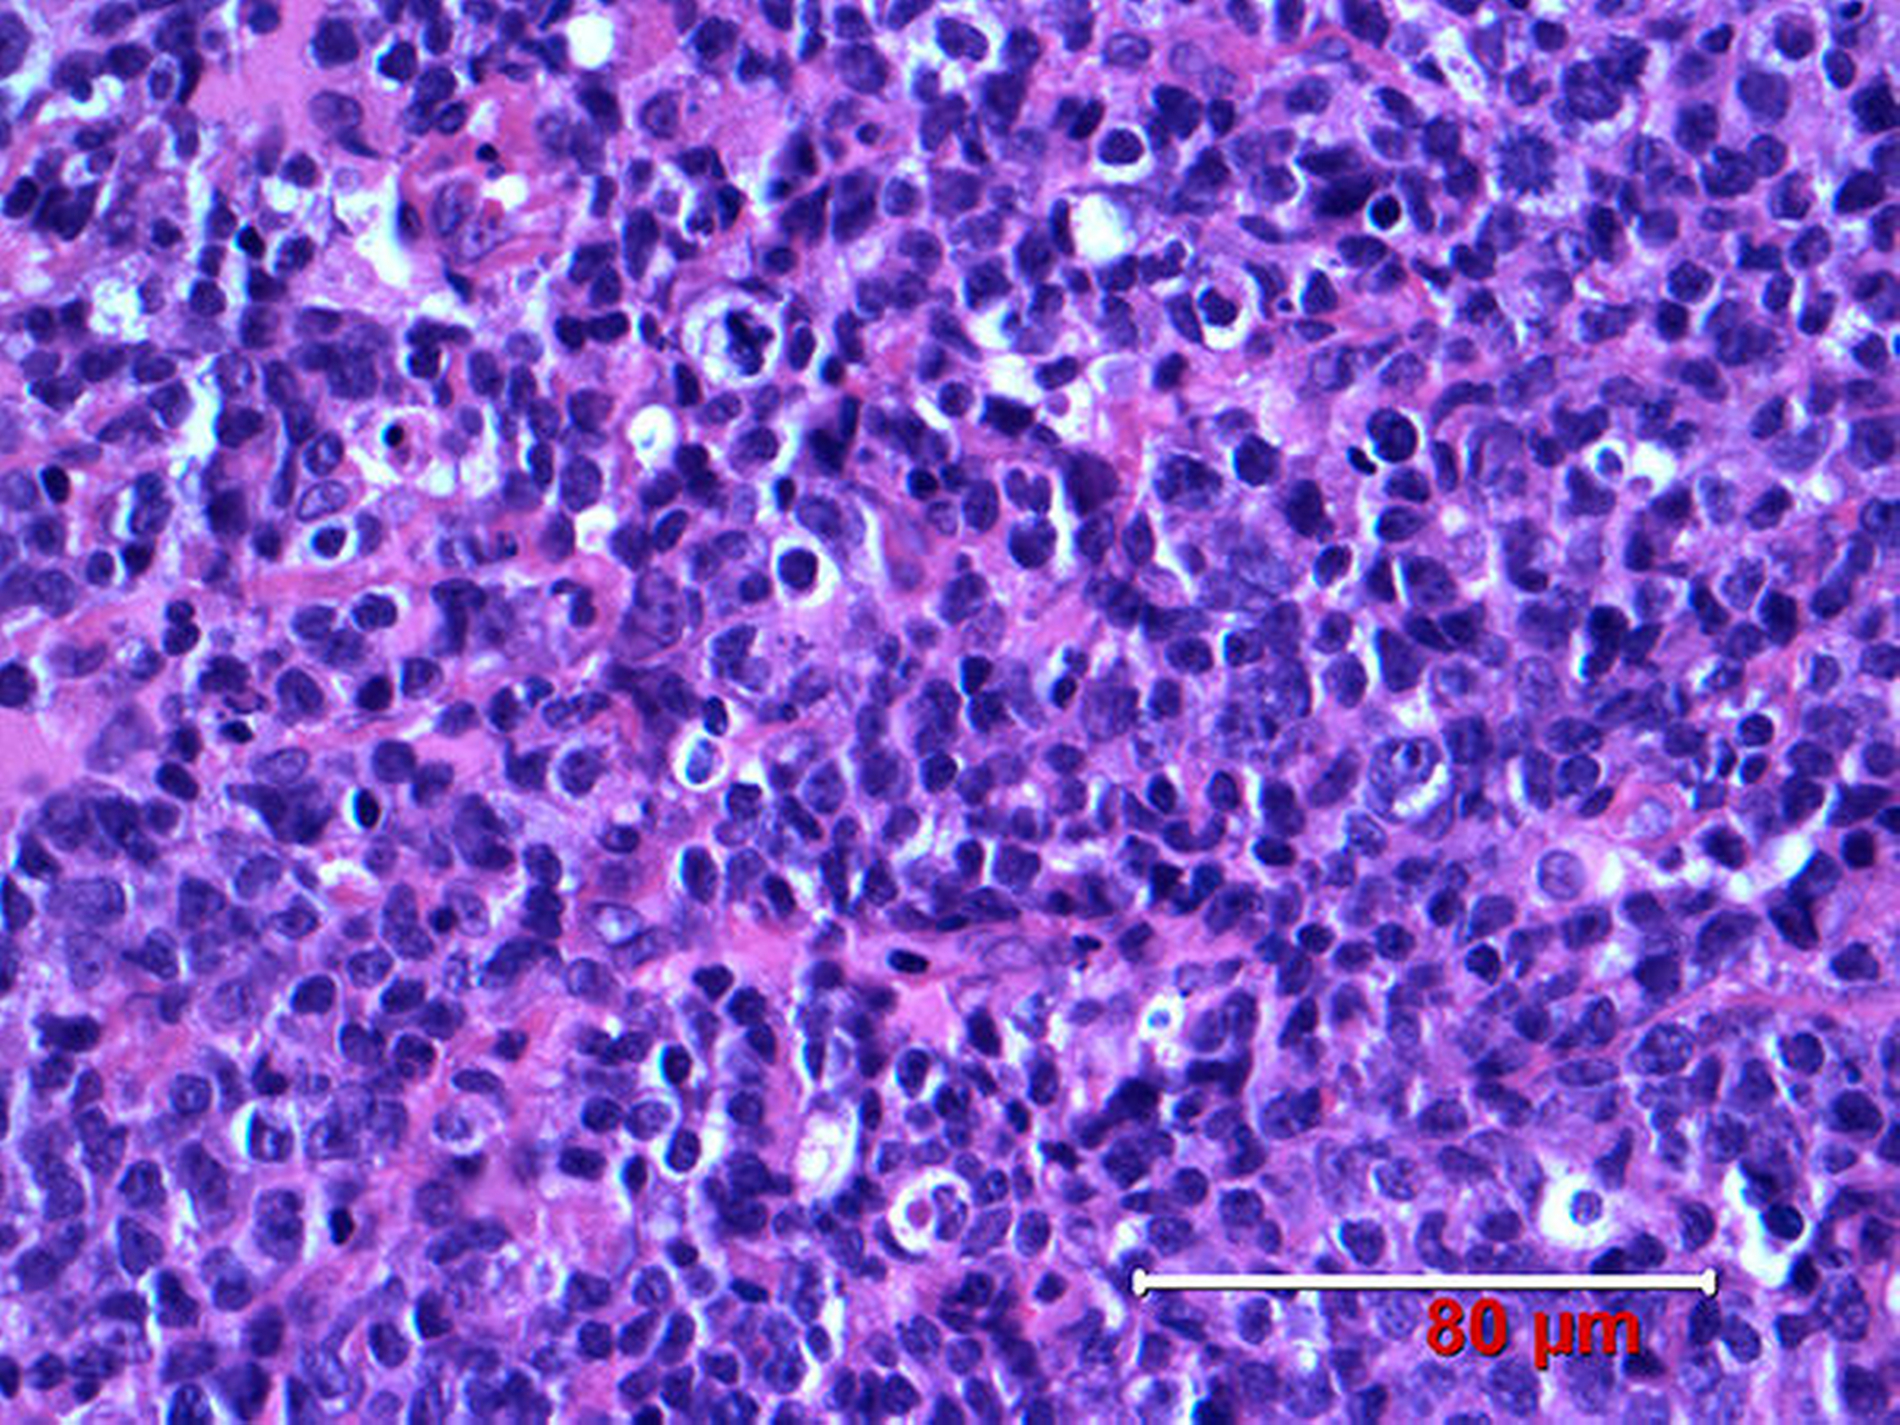

Es erfolgte daraufhin eine operative Revision mit Probeentnahme cervical über einen extraoralen Zugang sowie eine Biopsie von intraoral mit Tumorinspektion. Die pathohistologische Begutachtung ergab ein hochmalignes Non-Hodgkin-Lymphom der B-Zell-Reihe, entsprechend einem diffusen großzelligen B-Zell-Lymphom der WHO-Klassifikation (Abbildung 4).